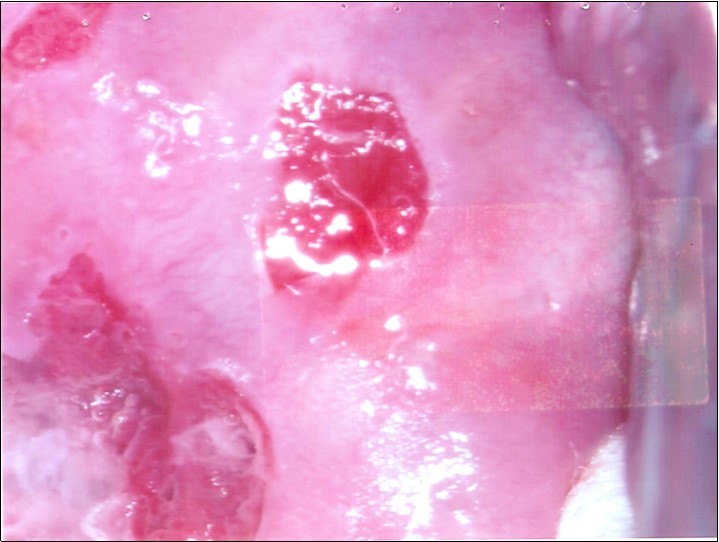

At initial presentation, colposcopy was unsatisfactory due to inadequate visualisation of the transformation zone. (Figure 1) Severe cervico-vaginitis was seen, with frothy white discharge and contact bleeding. A small focus of aceto-white epithelium was seen at the 1 o’clock region surrounded by peeling, friable epithelium. HPV DNA test, as well as cervical punch biopsy of the focus of aceto-white epithelium were taken.

Figure 1.Initial colposcopy

Initial colposcopy